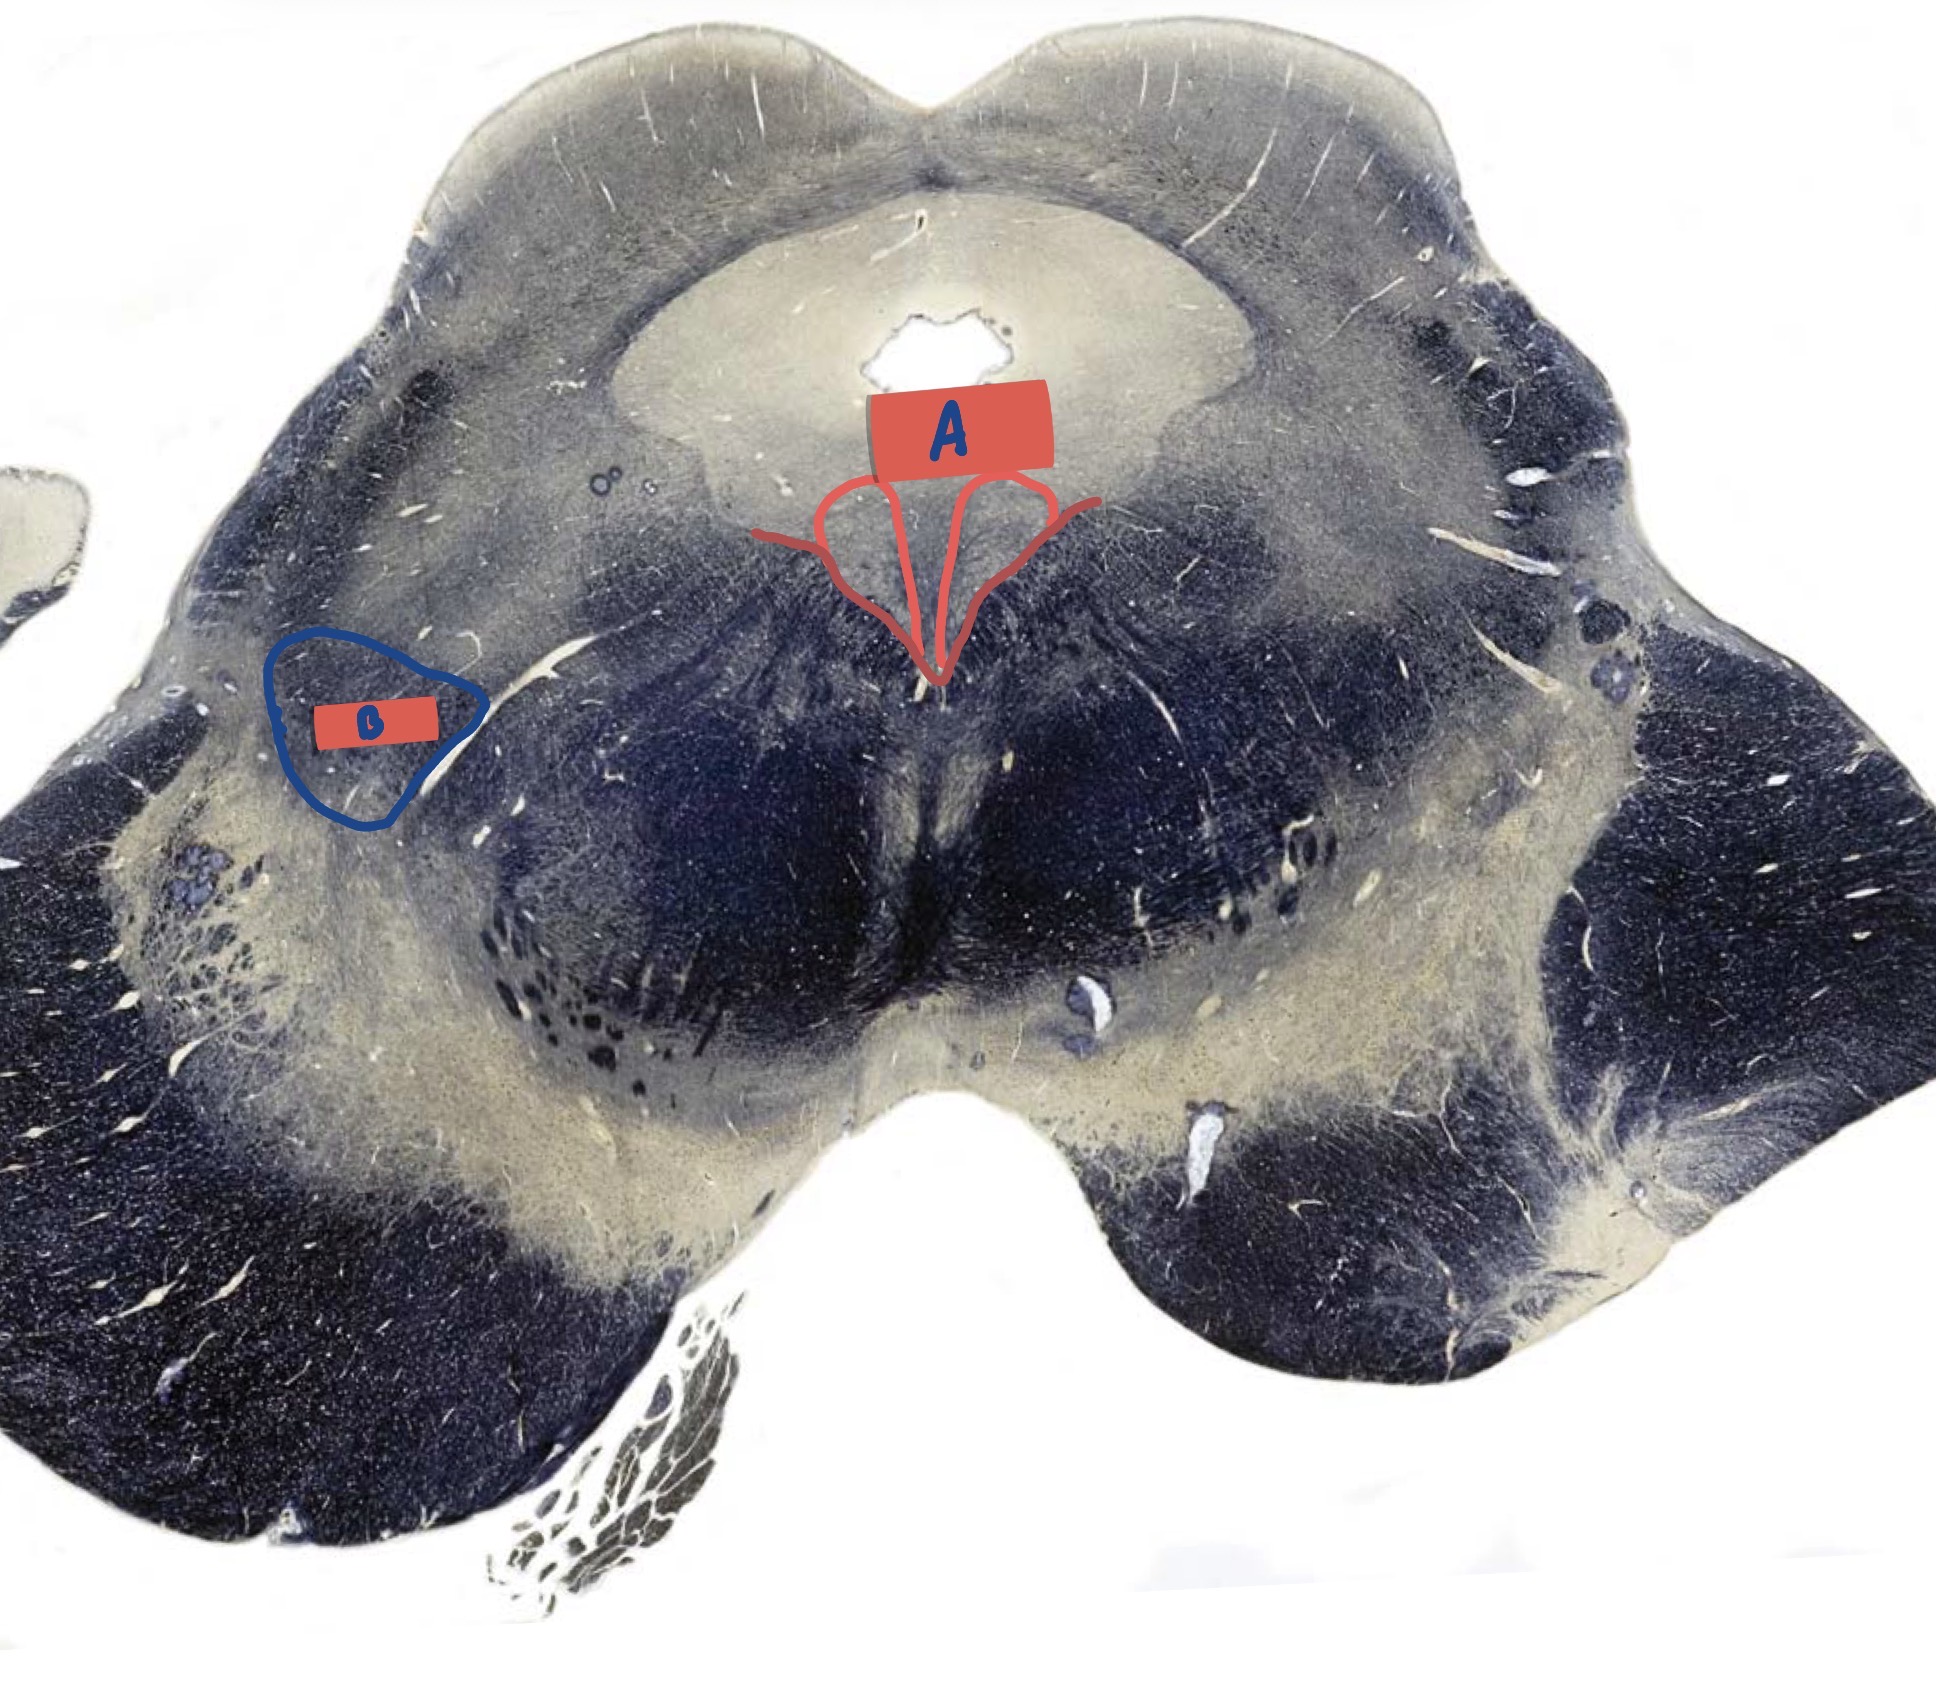

What is A?

Hypoglossal nucleus

What is B

Dorsal motor nerve of Vagus

What is C?

Solitary Nucleus

What is D?

Nucleus ambiguus

What is E?

Medial lemniscus